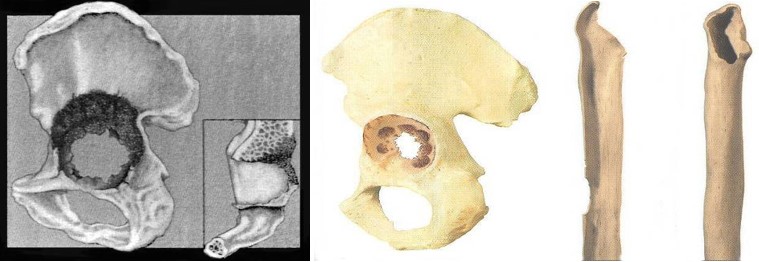

Найважливішою з проблем ревізійного протезування є наявність у хворих дефектів кісткового ложе протеза, як результат гранулематозного запалення, що виникає під дією продуктів зношення та руйнування пари тертя.

В своїй роботі ми класифікацією кісткових дефектів ложе нестабільнокористувалисяго протеза колінного суглоба за AORI (Anderson Orthopaedic Research Institute, USA), 1997 де автори виділяють 3 типа кісткових дефектів

Тип 1 – інтактна кістка (intact metaphysealbone) – невеликі кісткові дефекти, зазвичай без пошкодження кортикальної кістки. Характеризується нормальною кісткової структурою і збереженням губчастої і кортикальної кістки метафиза, нормальним рівнем суглобової лінії. позначаються як F1 – для стегнової кістки і Т1 – для великогомілкової.

Тип 2 – пошкоджена кістка (damаged metaphyseal bone) – характеризується втратою губчастої і кортикальної кісткової маси метаепіфізів, без заповнення якої неможливе створення надійної опори для компонентів ревізійного імплантату і відновлення анатомічного рівня суглобової лінії. (F2 А та F2 Б – для стегнової і Т2 А та Т2 Б – для великогомілкової кісток)

Тип 3 – дефіцит кістки (deficient metaphyseal segment) – характеризується вираженою втратою губчастої і кортикальної кісткової маси метаепіфіза, без компенсації якої неможливе створення опори для компонентів ревізіційного імплантату і відновлення нормального рівня суглобової лінії. Дефекти частіше поширюються до надвиростків і вище на стегнової кістці або до горбистості і нижче на великогомілковій кістці. (F3 А та F3 Б – для стегнової і Т3 А та Т3 Б– для великогомілкової кісток)